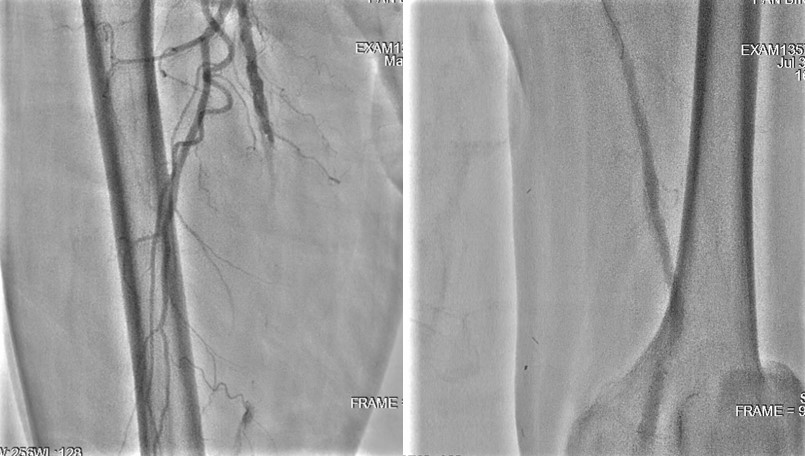

We tried wiring to left ICA occlusion with microcatheter first but failed.Then we tried PTA for right CCA occlusion. With microcatheter support, Gaia 2nd wire advanced to right ICA difficultly2.0mm small balloon pre-dilateddistal filter placement then carotid stenting smoothly.Patient symptoms improved dramatically and discharged 4 days later.We tried elective PTA for right SFA CTO by bilateral puncture approach. Antegrade from left transfemoral cross over sheath, and retrograde from right POPA.Antegrade failed wiringThen retrograde wire successfully advance to antegrade microcatheter -> Rendezvous -> externalization -> balloon pre-dilate and stenting